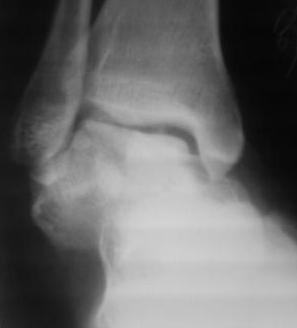

[Ortho] Оскольчатый перелом таранной кости

Поступил  б-ной, 1965г.р., вчера  упал  с высоты. В травм. пункте

произведена репозиция. наложена  гипсовая повязка. Обратился с сильными

болями в  стопе, срочно  рассечена гипсовая  повязка, выраженный

отек стопы, сплошные  фликтены, конечность  уложена  на  шину

Белера, скелетное  вытяжение за  пяточную  кость, антибиотики,

анальгетики, клексан, трентал.

Уважаемые  коллеги, что  делать?

1.Сразу  готовиться  к  артродезу?

2.Или  постараться  открыто  собрать осколки?(тогда вероятность

асеп.некроза большая)

3.Дистракцион.остеосинтез  А.В.Ф.,и дальше  время покажет?

Р-снимки  прилагаются.

Имя     : SP_A0163.jpg